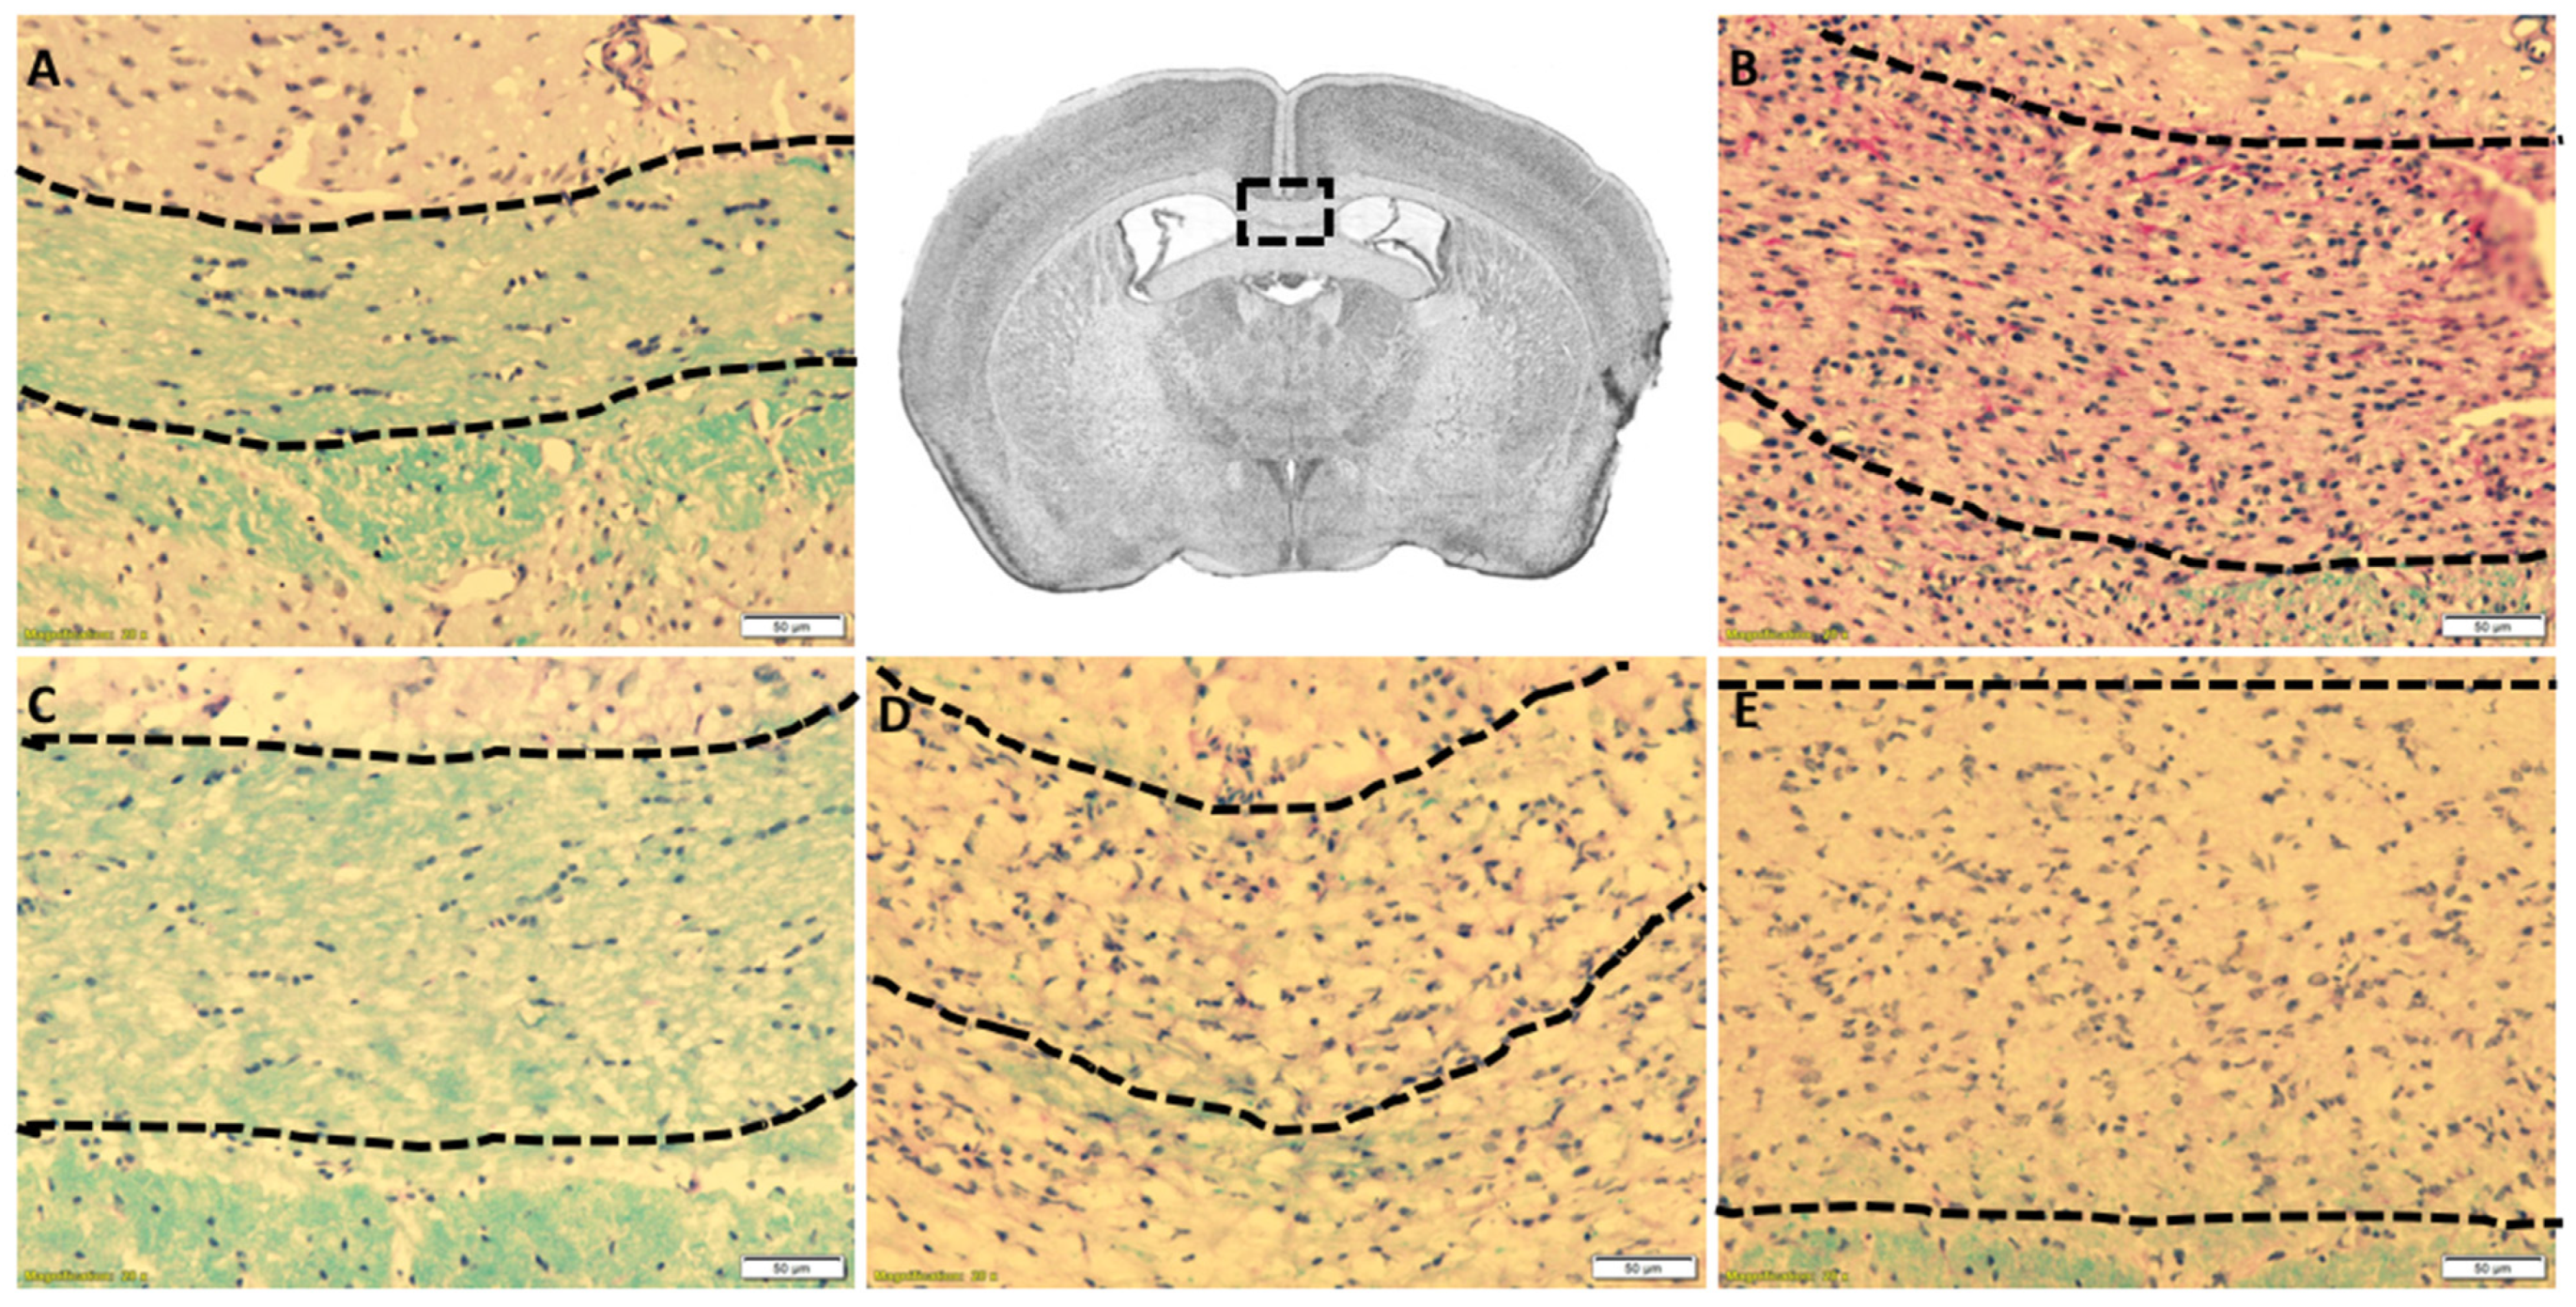

The cuprizone intoxication model consistently shows demyelination in the CC beginning at week 3.5 and ending in full demyelination by week 5.0, most consistently at the level of the fornix. Figure 2A shows control mice not exposed to Cuprizone, revealing fully myelinated (blue stained fibers) within the CC, whereas mice exposed for 5 weeks were fully demyelinated, showing negligible amounts of myelin (Figure 2B). Furthermore, mice not exposed to cuprizone showed no detrimental effect on normal myelinated CC. Importantly, mice exposed to cuprizone for 3.5 week (faint amount of blue-stained fibers) demonstrate partial demyelination (Figure 2D,E), while full demyelination is noted post 5.0 weeks of CF as well as increased cellularity from MM (Figure 2B). These data suggest the induction of demyelination occurred as predicted and suggest the 18F-PBR-111 had no obvious detrimental effects on a myelinated CC. The results imply that sterile inflammation manifested by MM accumulation is present in CF mice.

Figure 2. Cuprizone-induced demyelination of the corpus callosum in 18F-PBR-111 injected mouse brain sections. Representative image in the first row, center box, demonstrates the area of analysis. LFB-PAS staining of control (A) and 18F-PBR-111 injected (BE) mice after 0 (A,C), 3.5 (D,E), and 5 weeks (B) after cuprizone treatment was used to analyze myelin levels (blue) and cellularity from MM (dark purple nuclei). Hand-drawn dotted lines represent the area in which scoring for myelin and cellularity was conducted. White scale bar represents 50 microns.